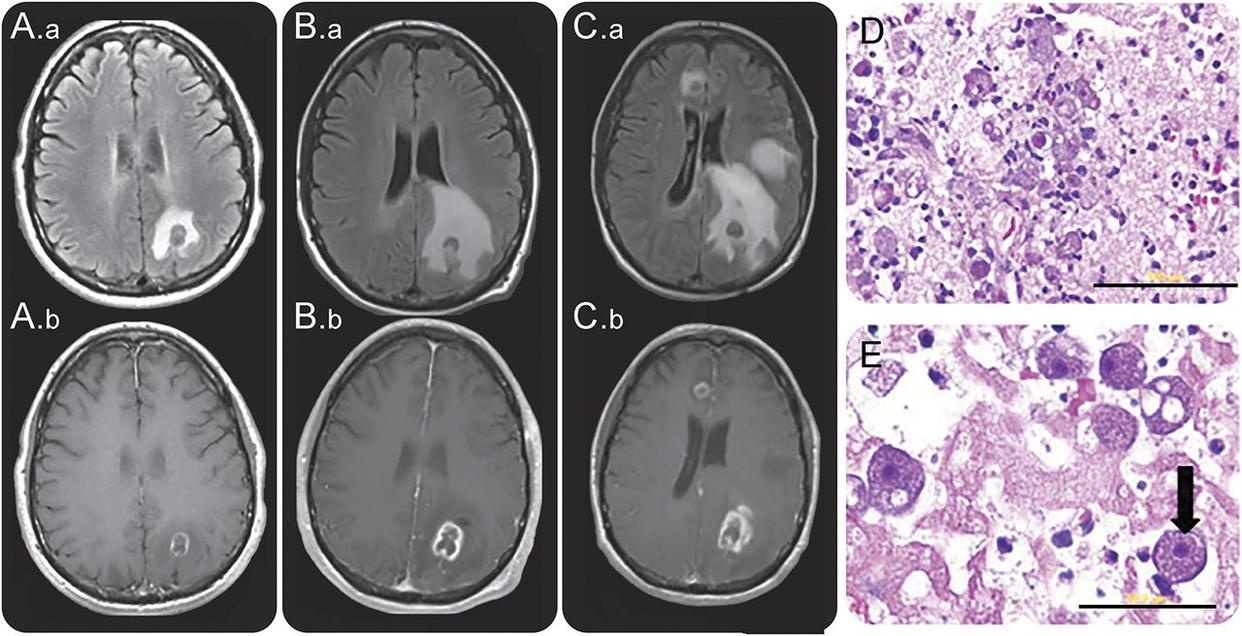

最终到了贵阳某儿童医院后,该医院在6月21日给小丁下达了病危通知书,诊断显示小丁急性化脓性脑膜炎,出现持续癫痫、中枢性呼吸衰竭、支气管肺炎等症状。到了6月25日,小丁的脑脊液检测结果出来了,终于确定了让小丁变成这样的罪魁祸首——狒狒阿米巴原虫。

国家传染病医学中心、复旦大学附属华山医院感染科曾通过官方公众号“华山感染”,发布了我国的一个叫阿文的15岁孩子因为感染狒狒阿米巴原虫,然后被狒狒巴拉姆希阿米巴脑炎夺走生命的案例。他也是因为游泳被感染的。

狒狒阿米巴原虫(Balamuthia mandrillaris)是一种新兴的机会性原生动物病原体,是自由生活的变形虫群体的成员。它会引起严重的皮肤感染和涉及中枢神经系统(CNS)的致命性脑炎,病死率>98%。目前人类对其发病的机制和病理生理学都未完全了解。尽管尝试了多种治疗手段,但效果还是极差,人类迫切的需要改进抗菌化疗和替代策略来开发治疗干预措施。

狒狒阿米巴原虫首次发现于1986年的加州圣地亚哥动物园野生动物公园。当时有只狒狒因为出血性脑炎死亡,医生经过病理生理检查,首次发现了狒狒阿米巴原虫。通过光学和电子显微镜研究、动物致病性测试、抗原分析和rRNA序列等手段,最终确定这是一种新属的阿米巴原虫,属名被命名为Balamuthia。之后从1991年开始,研究者陆续发现了多起涉及中枢神经系统的致命人类感染都跟狒狒阿米巴原虫有关。